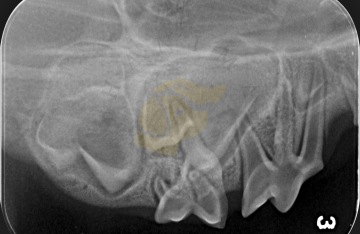

Intraorální rentgen – když zub není vidět

V případech, kdy některý zub není viditelný, ale není jasné, zda skutečně chybí, nebo je pouze neprořezaný, se používá intraorální rentgen. Tento typ snímkování umožňuje zjistit, zda se zub nachází v čelisti, ale z nějakého důvodu neprorazil dáseň (např. je impaktovaný nebo retenovaný).

Rentgen pomáhá určit:

Přítomnost zubu v čelisti.

Genetické chybění zubu (nezaložen).

Zda byl zub extrahován nebo ztracen v důsledku úrazu či nemoci.

Intraorální rentgen se provádí nejčastěji v sedaci nebo krátké anestezii, protože pes musí během zákroku zůstat zcela v klidu. Je to neinvazivní a velmi přesný způsob, jak doložit plnochrupost i v nejasných případech.